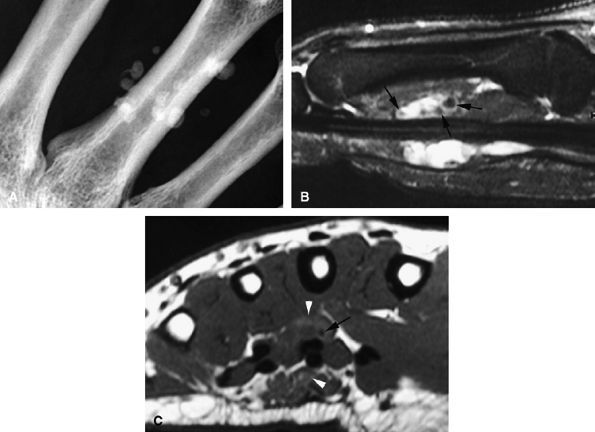

FIGURE 11.69 ● Sarcoidosis with osseous involvement (arrowheads). PA view radiograph (A) showing polycystic osseous involvement of the fingers. A sagittal 3D post-contrast gradient-echo image (B) and an axial post-contrast T1-weighted image (C) depict polysynovitis with joint synovitis (asterisks) and polynodular tenosynovitis (arrows).

|

![]() |

FIGURE 11.70 ● Chondromatosis of the sheath of the flexor tendons on (A) an axial fast spin-echo T2-weighted image and T1-weighted images before (B) and after (C) injection of gadolinium with fat suppression. There is enlargement of the tendon sheaths of the third and fourth fingers with synovitis (arrows) and cartilage signal characteristics (asterisks). (D) Surgical exposure indicating white cartilage nodules (asterisks).